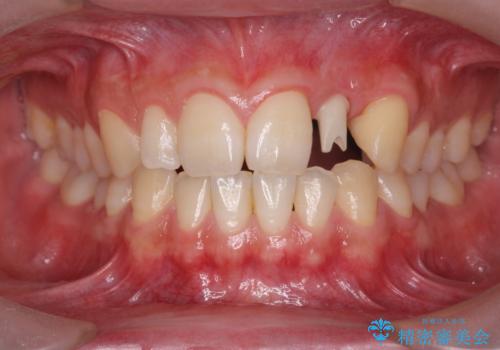

前歯部 インプラント治療

- 前歯の永久歯が元々なく、乳歯を失ったタイミングで前歯の審美性の回復を求めて来院されました。

機能・審美性の回復手段として、インプラント治療・ブリッジ・部分床義歯が考えられます。

それぞれの治療に特徴がありますが、取り外しの必要がなく隣の歯を削る必要も必要ないインプラント治療を選択されました。

前歯部にインプラントを埋入し、きれいに仕上げるためには骨の造成技術や歯肉の厚みを増すような処置を行い、インプラント周囲の環境を整備することが肝要です。